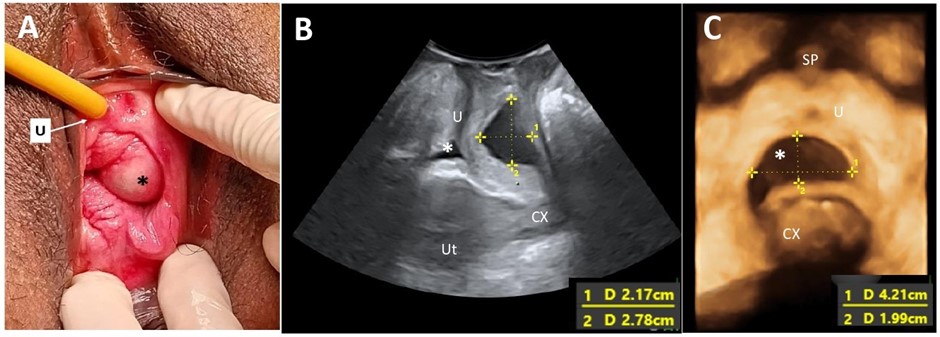

FIGURE 1: (A) A left periurethral mass extending from the left periurethral space to suburethral region measuring 3 cm x 5 cm; (B) Midsagittal view of the pelvic floor showing a cystic mass (*) dorsal to the urethra (U) measuring 2.17 cm x 2.78 cm on translabial perineal ultrasound (TPUS); (C) TPUS view demonstrating a periurethral mass dorsal to the urethra measuring 4.22 cm (width) x 1.99 cm (vertical dimension). (SP: Symphysis pubis; Ut: Uterus; CX: Cervix)